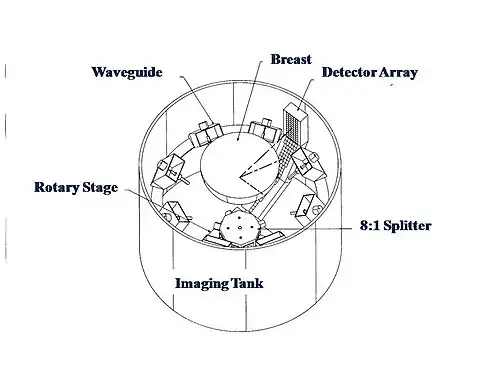

Microwaves have also been used to form 3D thermoacoustic images of the human breast. One of the first devices to do so is depicted in Fig. 10. It consisted of an array of eight waveguides, which directed microwave energy into the breast. A transducer array was rotated in synchrony with the waveguides in order to acquire sufficient data to reconstruct the internal structures of the breast. Figure 11 shows an animation of the typical glandular tissue pattern in a normal breast.